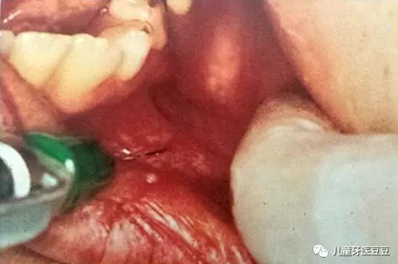

PX@H0N%[00B]78IX(J1V]`4.png

口腔局部浸潤麻醉